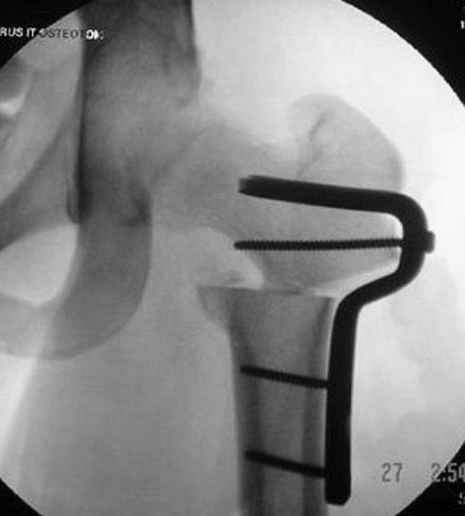

Несколько снимков из моей коллекции, чтобы разьяснить, почему мы до сих пор делаем различные варианты остеотомии.

На рисунке N1 предоперационный план лечения ложного сустава шейки бедра- линия ложного сустава, угол и направление введения импланта, клиновидная остеотомия в градусах и миллиметрах, второй снимок после коррекции, расчет, на сколько удлиняется конечность и размеры импланта;

N3 рисунок окончательный снимок, после операции моя рентгенограмма должен выглядеть примерно как эта картина. На N4 снимке клин перед удалением; N5 послеоперации 3 нед.; N6 окончательная рентгенограмма.

варус при проксимальном отделе 95 градусной пластиной.

Djoldas Kuldjanov 23 Ноябрь 2004, 18:21

пластическая модель; и коррекция бедра аппаратом Илизарова.